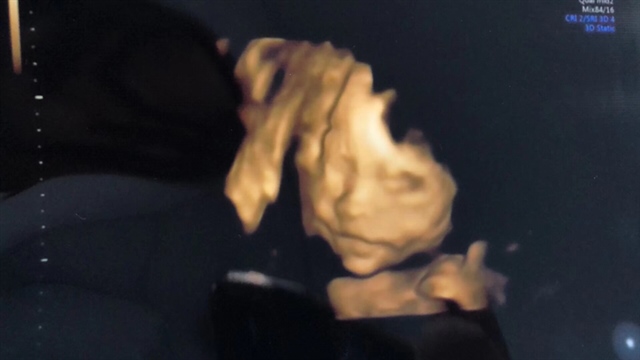

孕24周+3天

挺好哒